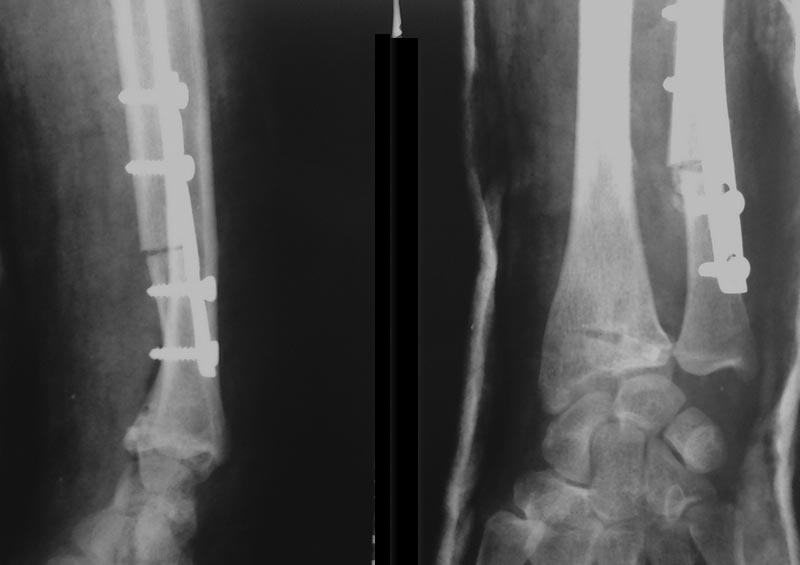

Мы для оценки луче-локтевого соотношения делаем снимок контрлатеральной конечности, можно простой оценкой определить объем резекции, можно и схему на кальке сотворить. Главное больше нужного не выбрать.Остеотомию выполняем осциллирующей пилой, можно и остеотомом с предварительным насверливанием тонким сверлом во избежание раскола.Укорочение локтевой кости способно устранить локтевой импинджмент синдром\Ulnar Impaction Syndrome\, который причиняет больше проблем пациенткам, чем косметический дискомфорт.В приложении послеоперационный снимок.

Имя     : RADIUS1a.jpg